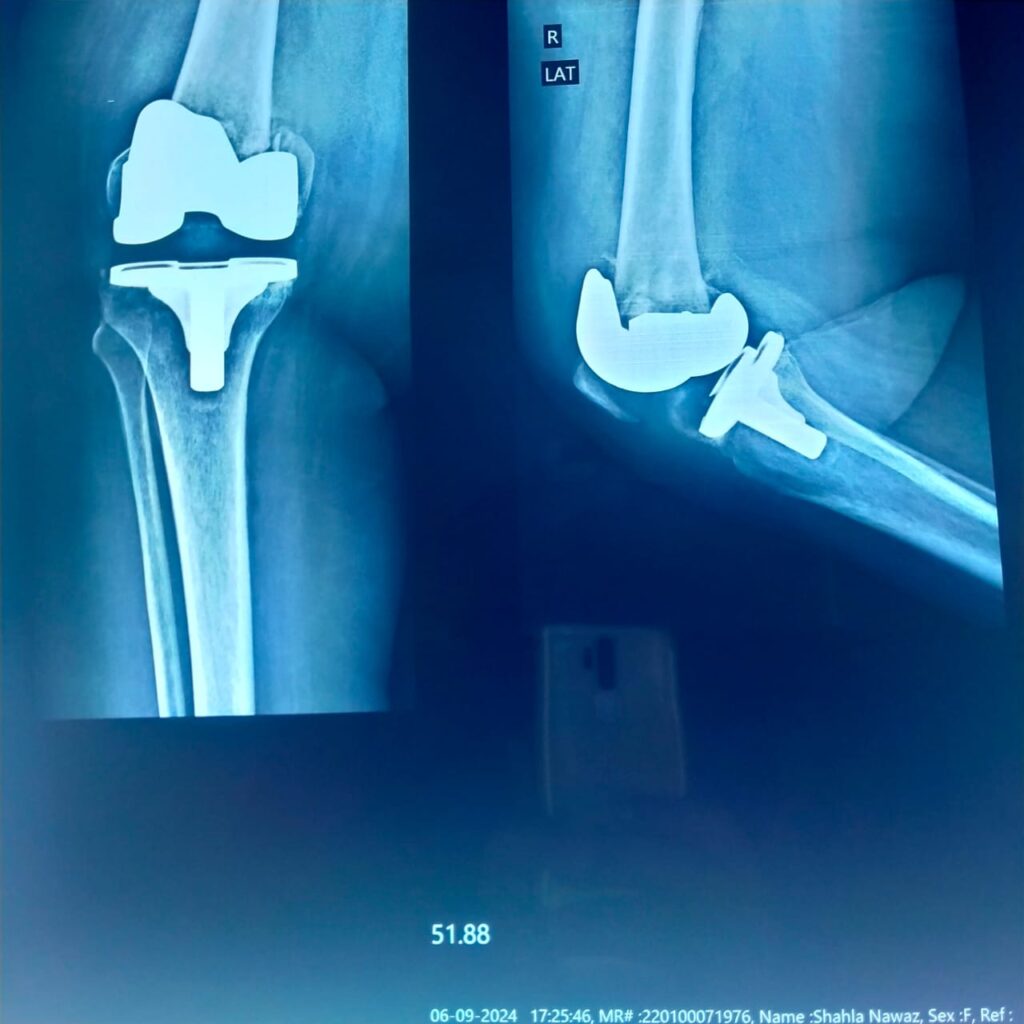

Revision Knee Replacement

When the prosthesis is loose or bone is severely damaged, revision surgery is needed. Long-stemmed implants provide stability and allow early weight-bearing.

This method is preferred for extremely distal fractures or when previous fixation has failed. It restores knee function and reduces pain.